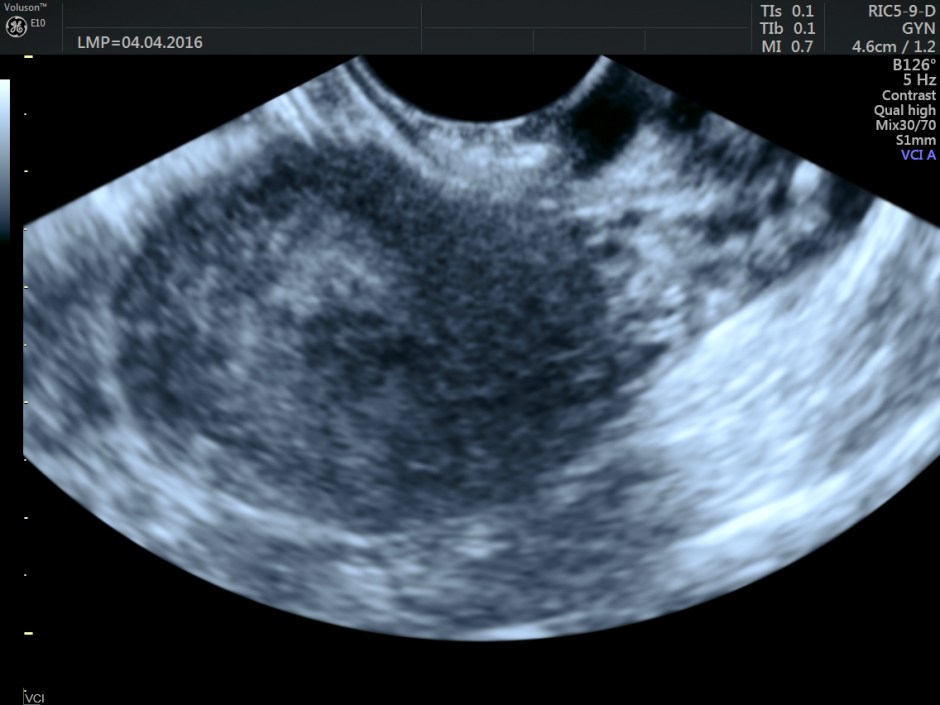

Volume contrast imaging pictures are given below:

Endometrium shows ? polypoid appearance; Irregular hypoechoic myometrial texture with some serpiginous appearance is seen.